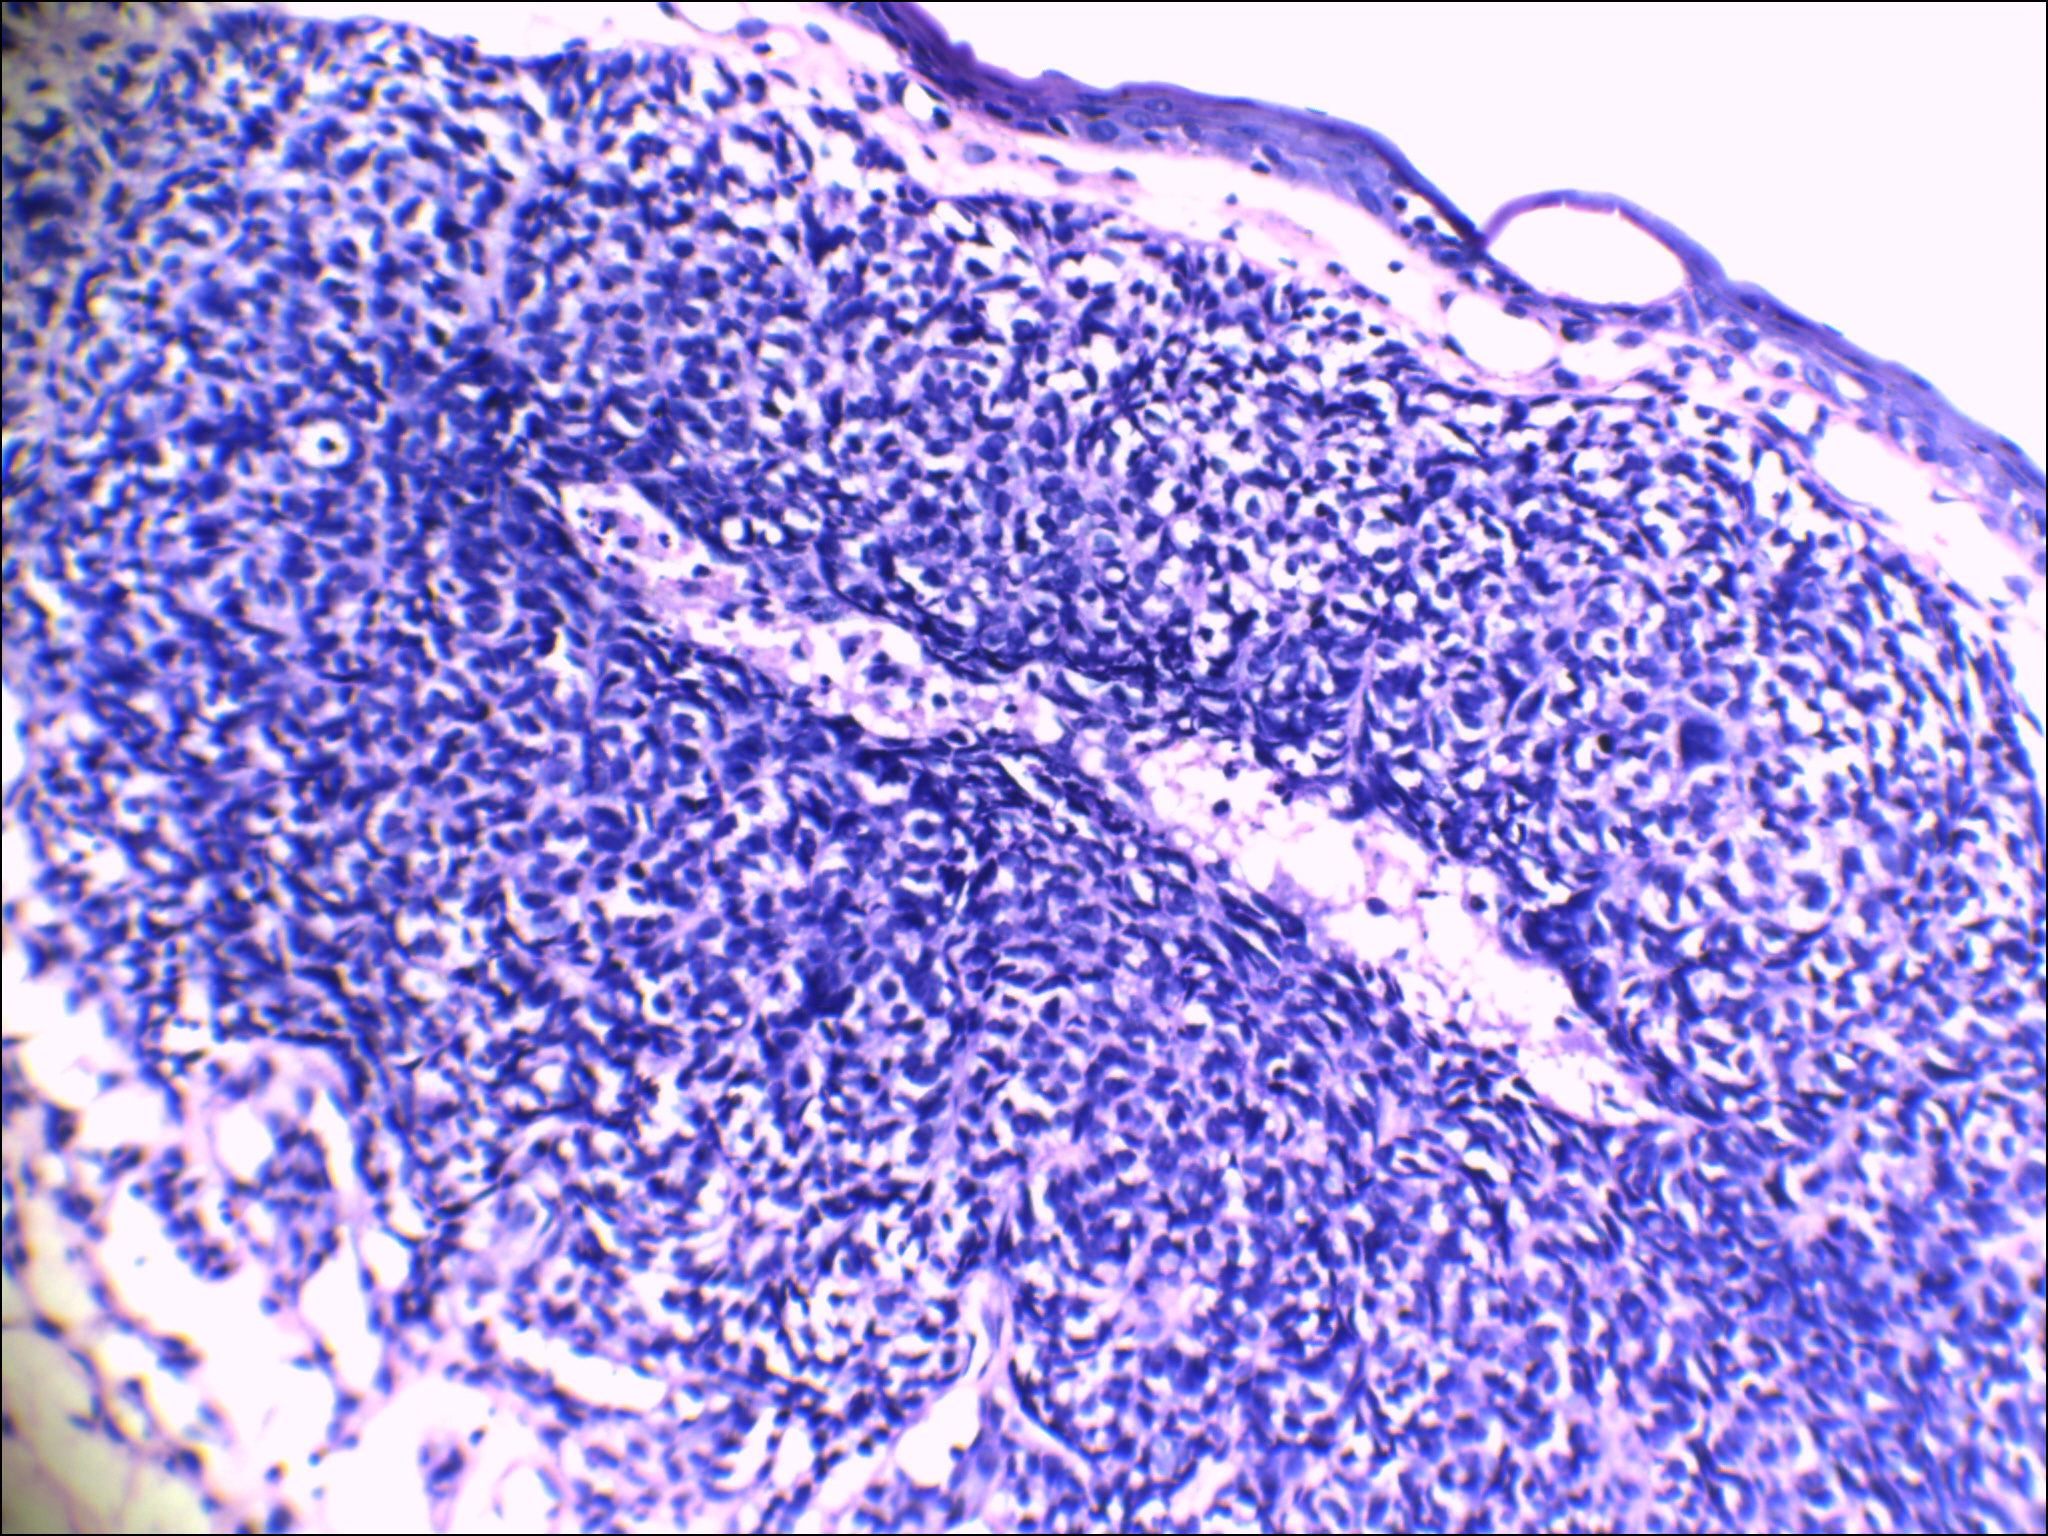

舌下皱褶区粘膜肿块

粘膜下透明、质软、固定的球样肿块,大小直径约0.2cm,表面无破溃。

粘膜组织一块0.5×0.5cm,表面见一突起0.3×0.3×0.2cm,切面灰白色。

建议:HMB-45

Warthin瘤?不是很典型